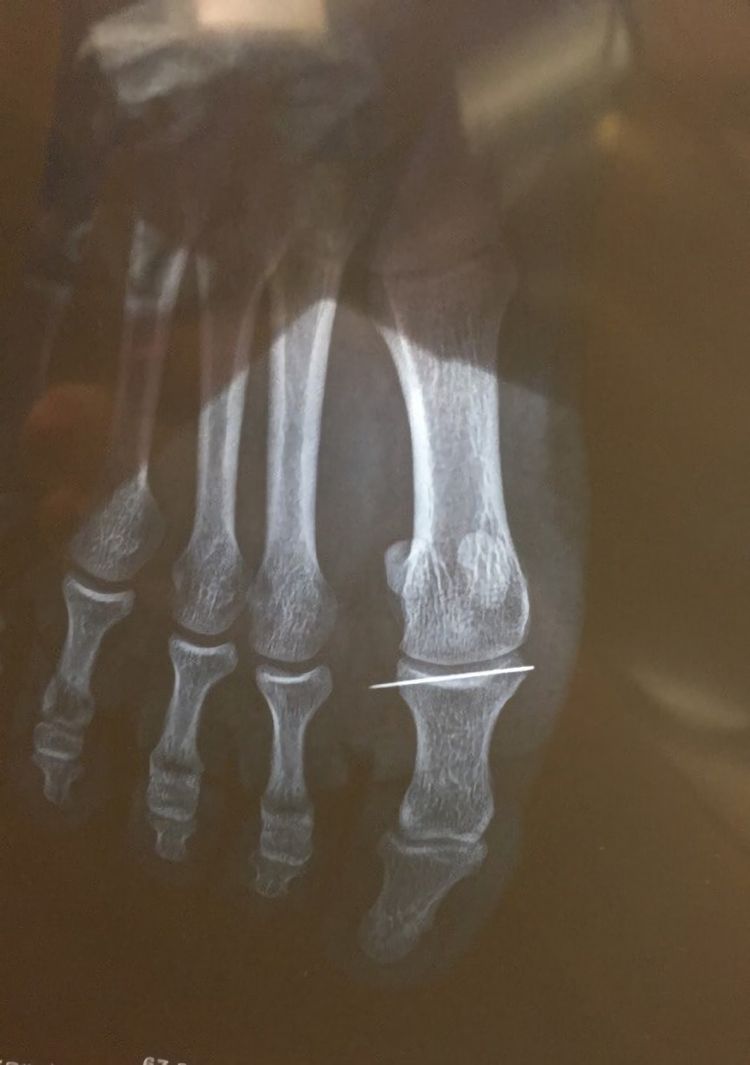

«Зашивал рубашку в гостиной. Почувствовал легкую боль, когда встал. Проигнорировал это, но через 3 дня едва мог ходить. Вот что показал рентген...»

Бедолаге повезло, что иголка не поломалась. Автор фото сообщил, что игла была успешно удалена: «Иглу извлекли благодаря бригаде, состоящей из 1 хирурга, 2 медсестёр и какому-то причудливому оборудованию, которое непрерывно просвечивало мою стопу во время операции..» 🧵